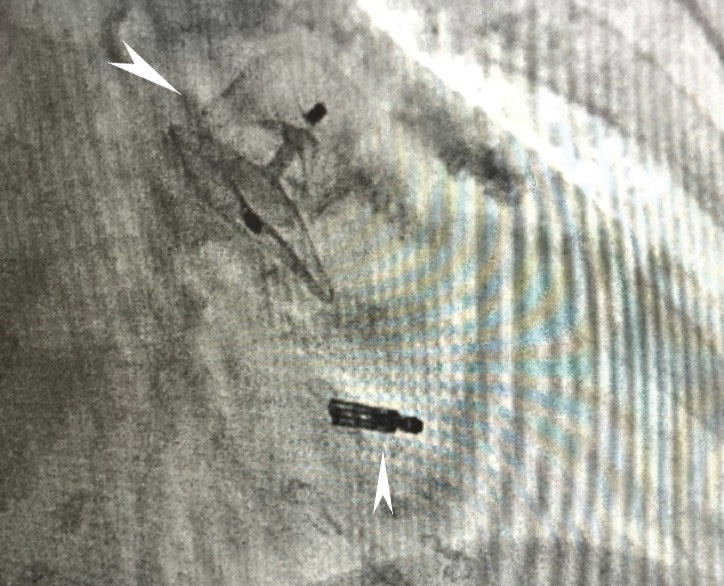

В связи с тяжелыми сопутствующими заболеваниями и высоким операционным риском принято решение о проведении малоинвазивной одномоментной операции. Под общей анестезией правым трансфеморальным доступом выполнена антеградная катетеризация нижней полой вены. На проводнике 0,035" в полость правого предсердия проведена система доставки иглы для транссептальной пункции. Под контролем чреспищеводной ЭхоКГ (ЧП ЭхоКГ) сделана пункция межпредсердной перегородки с последующим расширением пункционного отверстия. Игла для трансептальной пункции заменена на супержесткий проводник 0,035". Далее по проводнику в полость левого предсердия на 3 мм доставлен управляемый направляющий катетер для системы MitraClip 24 Fr. Под флюороскопическим и ЧП ЭхоКГ контролем клипса проведена и позиционирована в левом желудочке. Выполнен последовательный захват передней и задней створок МК. По данным ЧП ЭхоКГ достигнута оптимальная коаптация створок, регургитация до 1-й степени. Выполнено высвобождение клипсы MitraClip от системы доставки. На супержестком проводнике система доставки MitraClip (24 Fr) под контролем мануальной компрессии зоны чрескожного доступа заменена на систему доставки окклюдера Amulet (14 Fr). Выполнено контрастирование полости УЛП, далее в полость УЛП доставлен и имплантирован окклюдер Amplatzer Amulet 28 мм. При контрольной ЧП ЭхоКГ позиционирование окклюдера адекватное, раскрытие полное. Провокационная проба отрицательная, система доставки отцеплена. Доставочный интродьюсер извлечен, выполнен мануальный пассивный гемостаз, наложена асептическая давящая повязка. Касательно дезагрегантной и антикоагулянтной терапии, всего было введено 12 500 МЕ гепарина натрия, во время процедуры осуществлялось четырехкратное измерение ACT (activated clotting time – активированное время свертывания крови), целевые значения поддерживались в диапазоне 250–300 с. Вмешательство прошло без осложнений. Пациент экстубирован, переведен в отделение реанимации и интенсивной терапии для динамического наблюдения. Рентгенографический результат представлен на рис. 1, 2.

Рис. 1. Рентгенография после клипирования створок митрального клапана клипсой MitraClip. Селективное контрастирование ушка левого предсердия через систему доставки для оценки анатомии (указано стрелками)